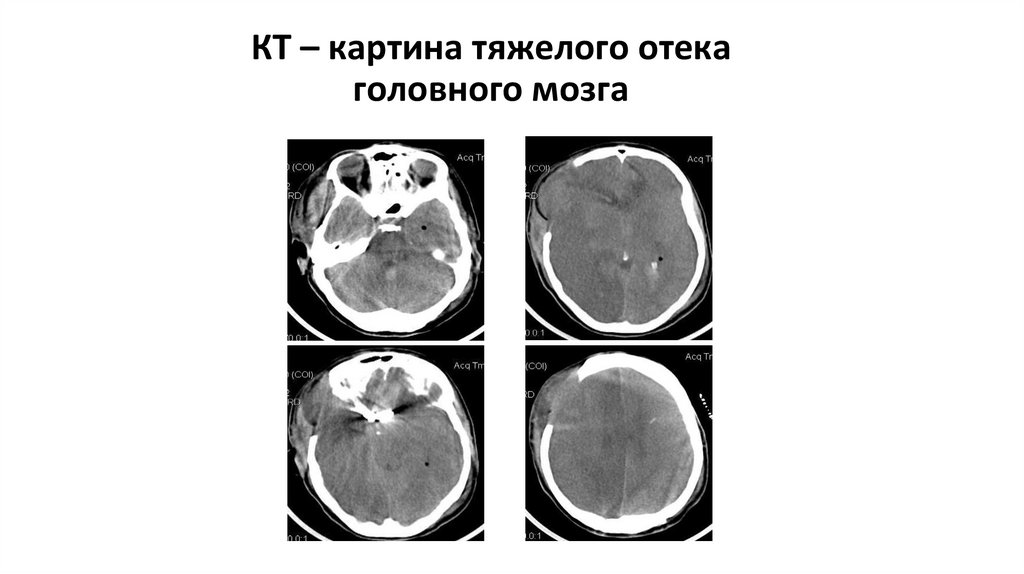

КТ – картина тяжелого отека головного мозга

65. КТ – картина тяжелого отека головного мозга